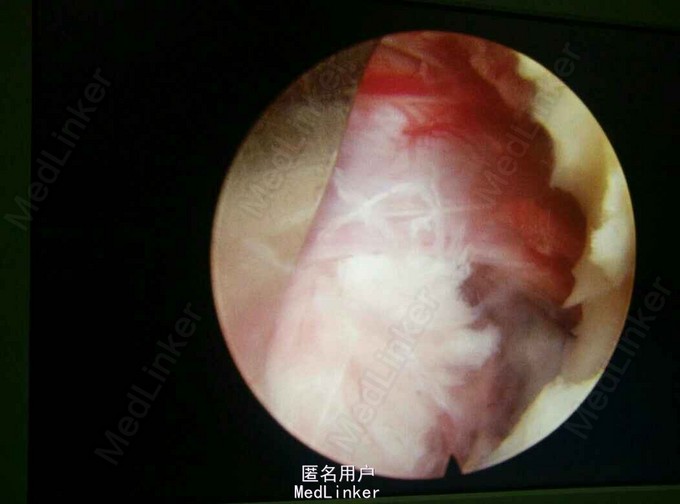

诊断:L5/S1椎间盘脱出(右侧) 治疗:因保守治疗效果不佳,准备行手术治疗。

请大家谈谈该患者的手术方案:开放融合内固定术?椎间盘镜手术?椎间孔镜手术?还是其他方案?